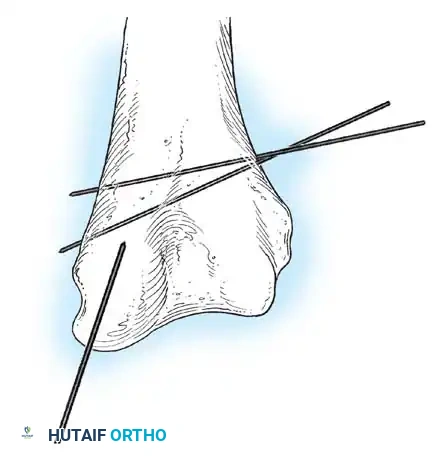

Percutaneous Leverage (Bernstein Technique)

Pesudo et al. and Bernstein et al. popularized the use of a percutaneous pin to manipulate the fracture fragments under fluoroscopy.

Anatomical Pitfall: During percutaneous reduction, the Kirschner wire must be introduced on the ulnar side of the radius. Introducing the wire laterally risks iatrogenic injury to the deep branch of the radial nerve (posterior interosseous nerve) as it traverses the arcade of Frohse.

Fig. 33-43 Radial neck fracture in relation to arcade of Frohse.